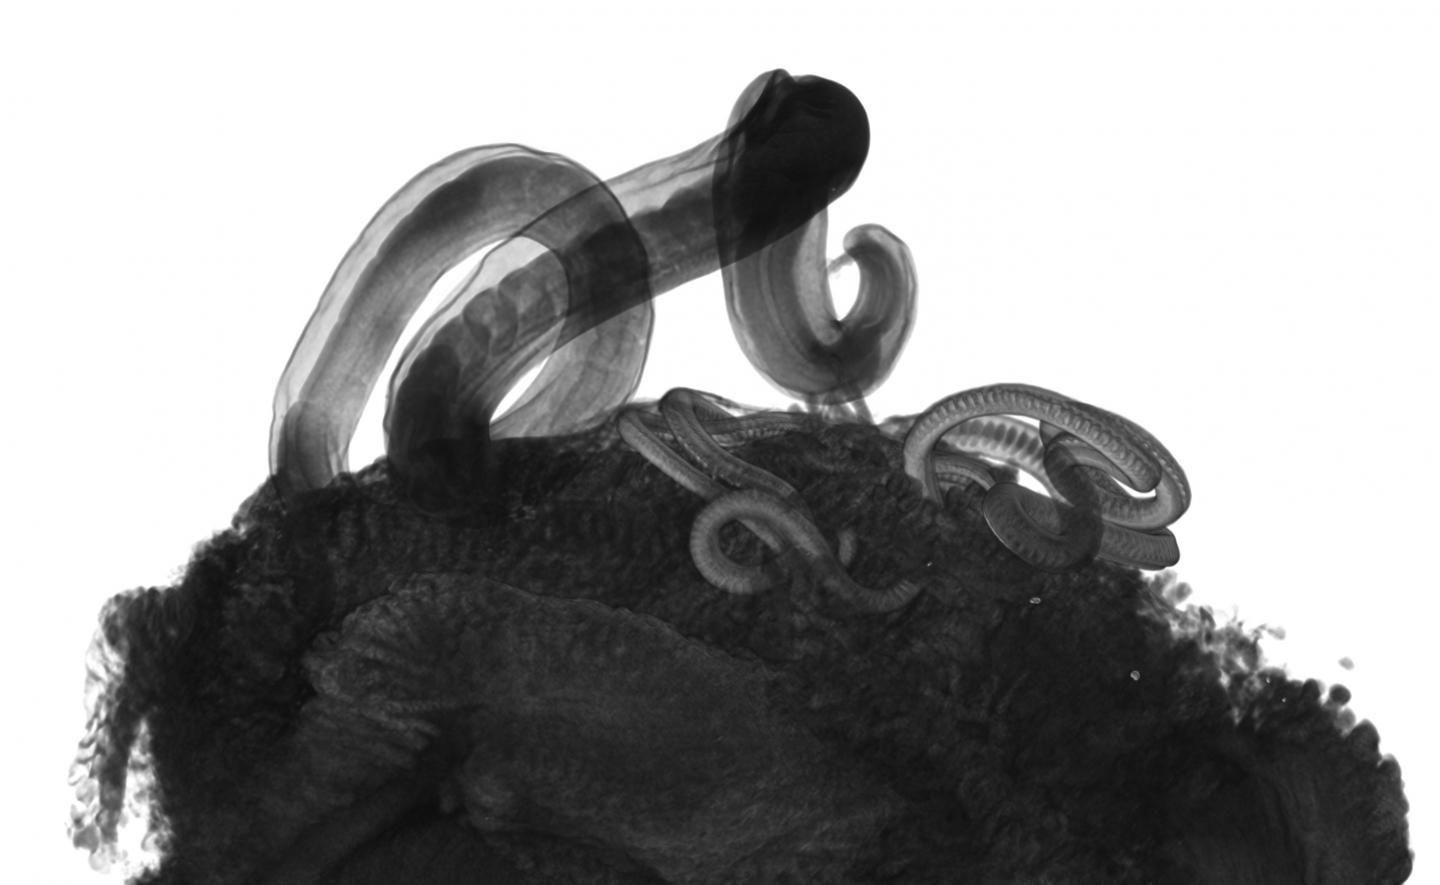

The human whipworm, which infects 500 million people and can damage physical and mental growth, is killed at egg and adult stage by a new drug class developed at the Universities of Manchester and Oxford and University College London.

Whipworm eggs are also affected by the compounds. Whipworm eggs are passed from infected faeces into people by hand to mouth contact. This often happens in unsanitary toilets or areas where people live close together. The eggs are highly resistant to extreme temperature changes and ultraviolet radiation and can remain viable in the environment for many years.

However the new compounds are effective against the eggs and could be developed into a spray which can stop infection at source.